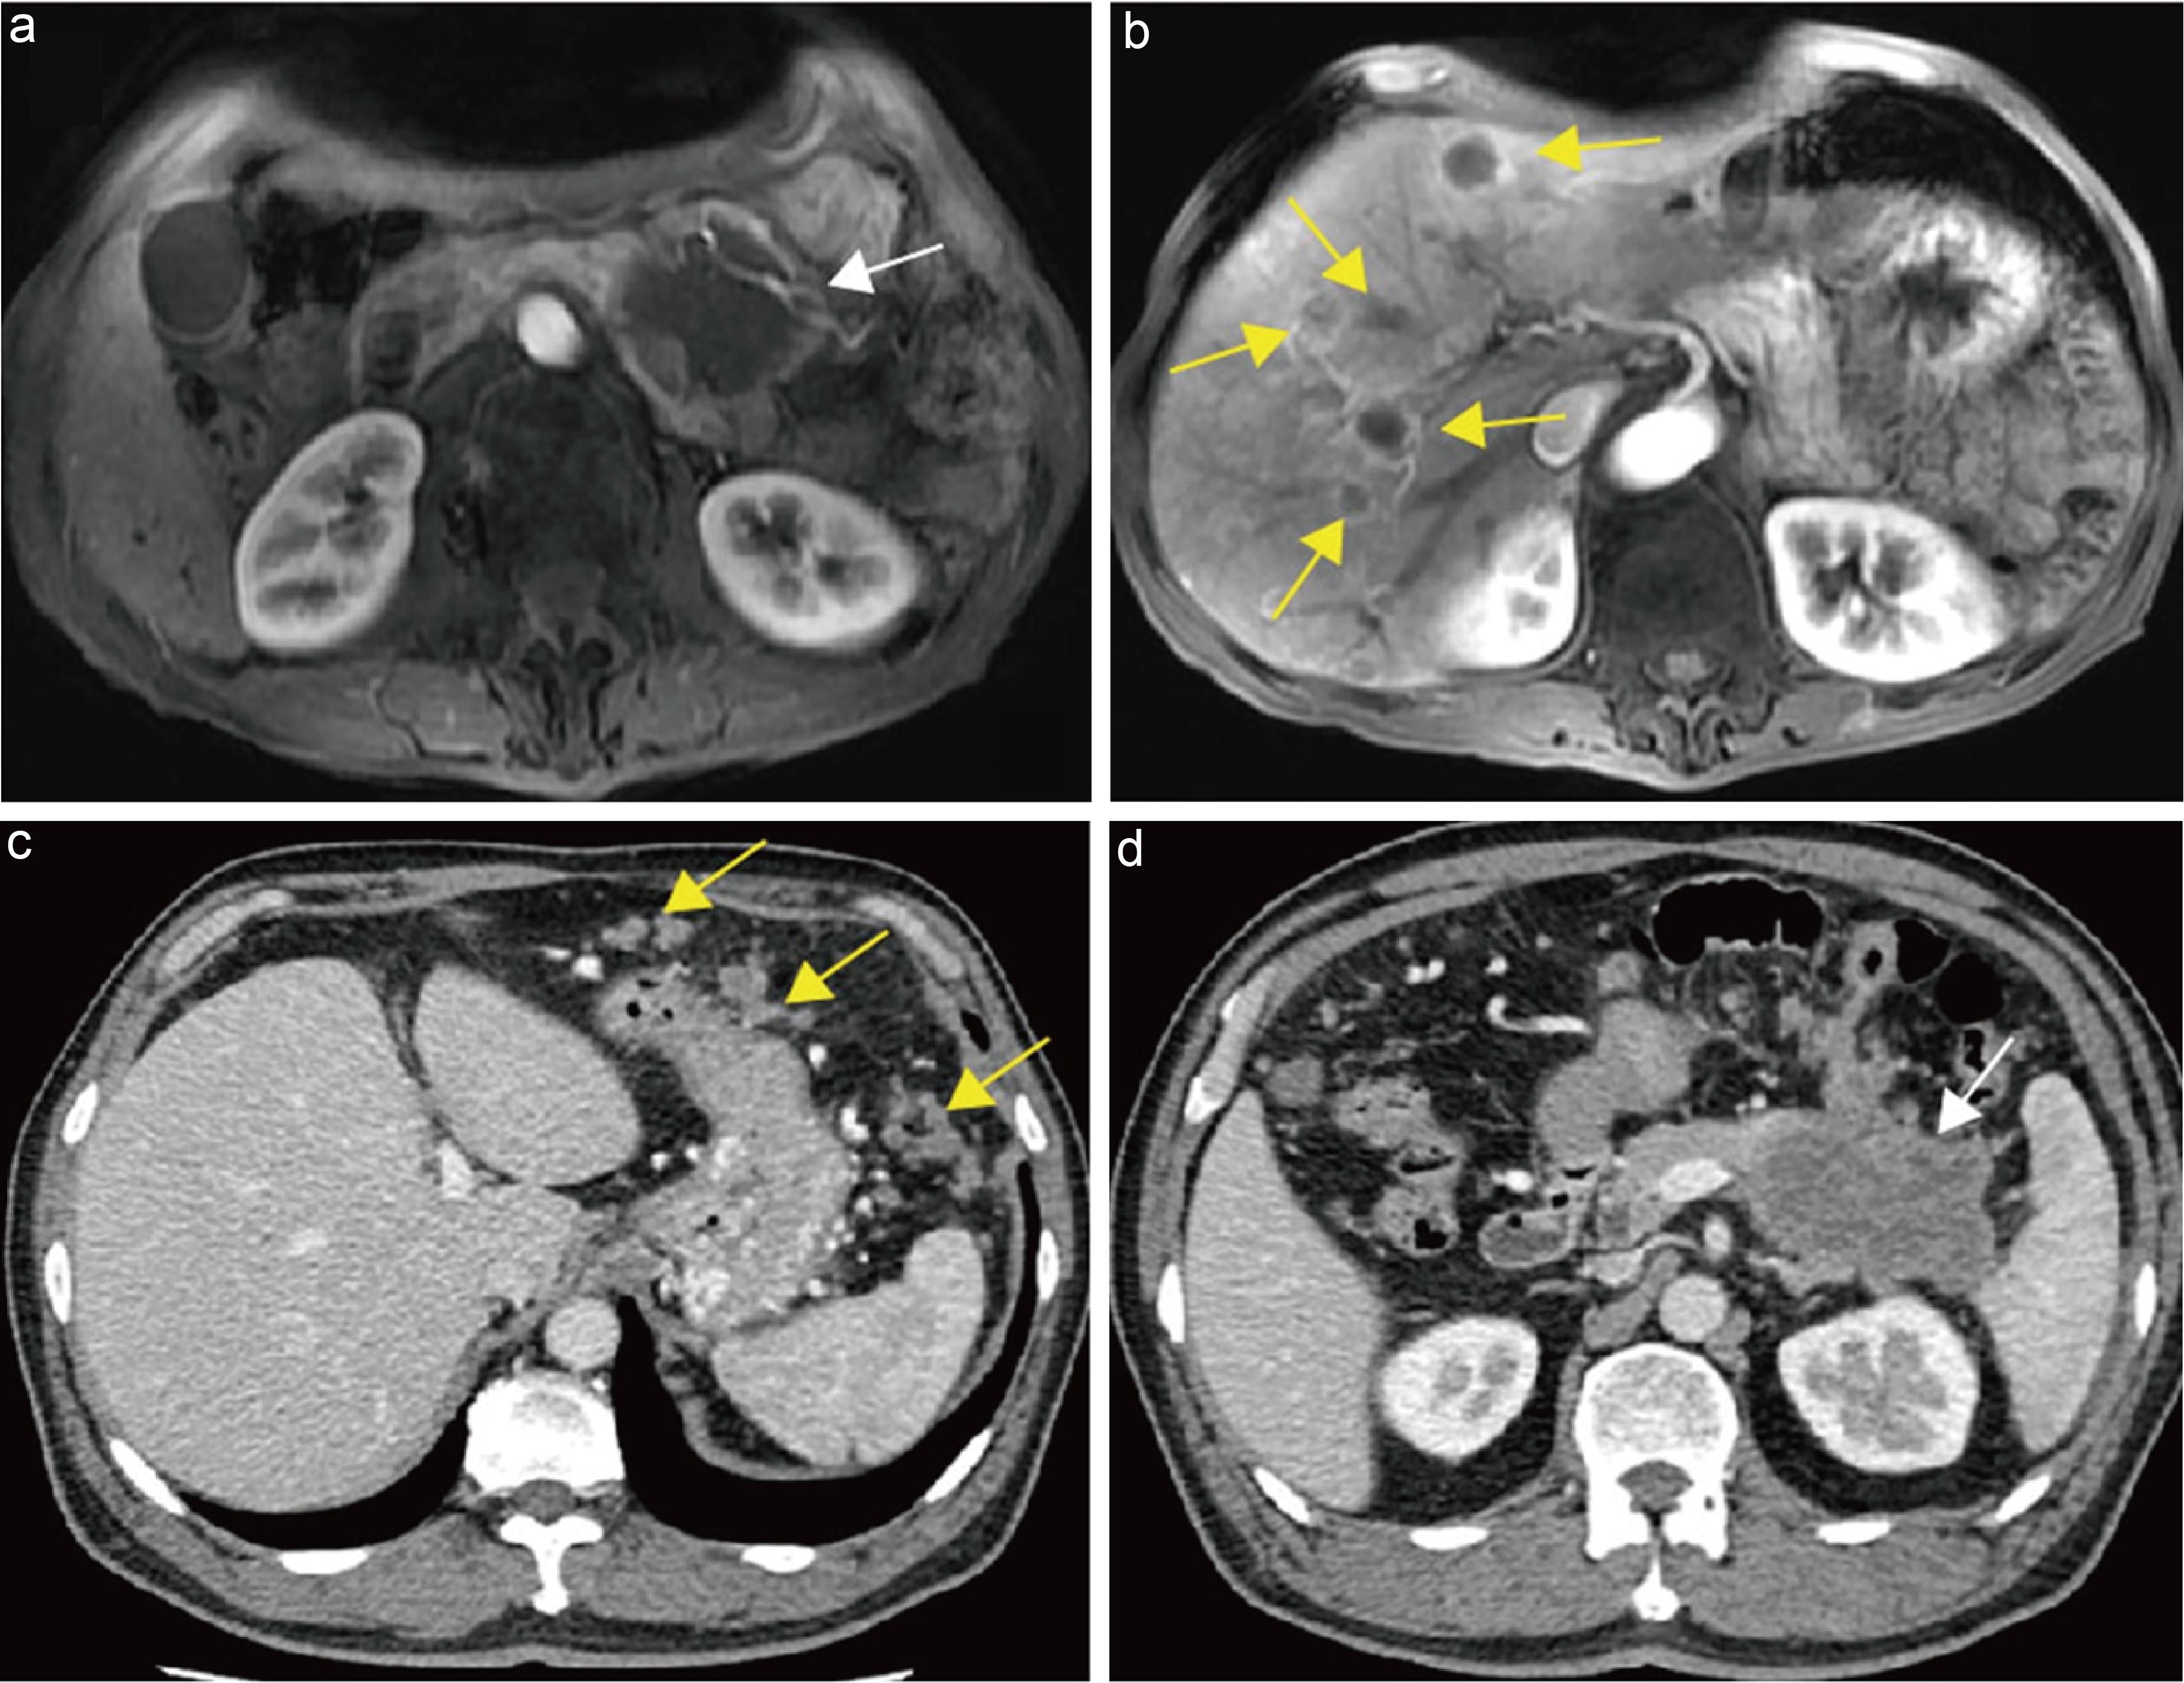

Currently, most studies consider the following imaging features suspicious for lymph node metastasis: short-axis diameter >10 mm, round shape, heterogeneous density/signal, heterogeneous enhancement, presence of necrosis, node confluence, indistinct margins, and restricted diffusion on MRI. The coexistence of multiple such imaging signs strongly suggests lymph node metastasis (Fig. 11).111,120,121

Imaging evaluation of lymph nodes in pancreatic cancer.

Fig. 11  Imaging evaluation of lymph nodes in pancreatic cancer.

(a) Axial arterial late-phase CT image showing a round, well-defined, homogeneously enhancing lymph node (short-axis ∼0.8 cm) inferior to the pancreatic head (yellow arrow); pathology was negative. (b) Axial arterial late-phase CT image showing a round lymph node with slightly low attenuation (short-axis ∼1.2 cm) inferior to the pancreatic head (yellow arrow); pathology was positive.